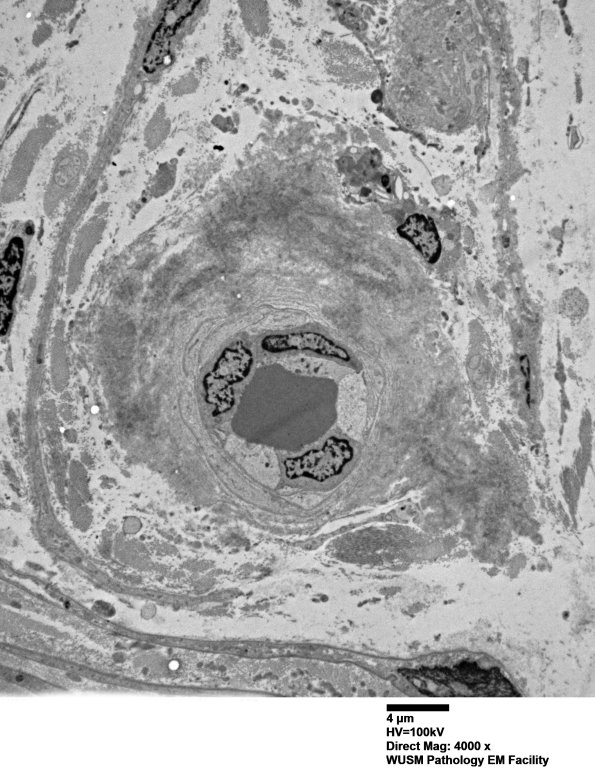

1G1,2 This small endoneurial vessel has a lumpy and irregular pattern of amyloid deposits. (electron micrograph)